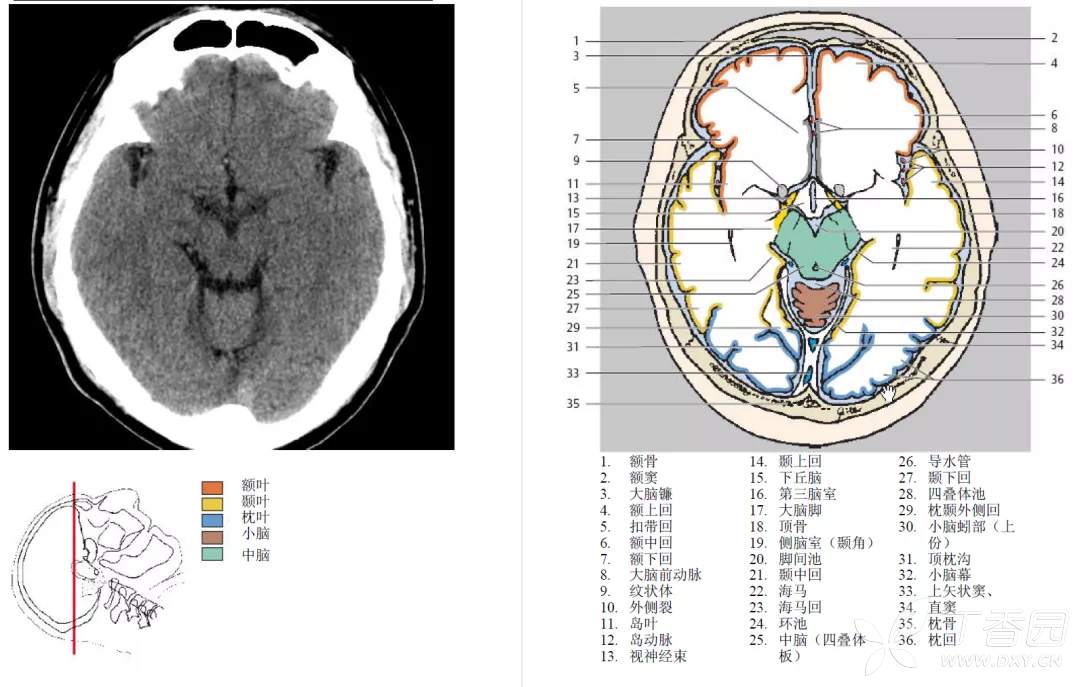

环池

环池 ambience cistern 分本部和翼部。

环池本部围绕中脑大脑脚两侧,连接于四叠体池和脚间池之间。

翼部向外伸向丘枕后下方,又名丘脑后池。

环池内有大脑后动脉、小脑上动脉、脉络丛前动脉和后动脉、基底静脉和滑车神经。

由四叠体池、环池和脚间池可勾画出中脑的轮廓。

鞍上池

位置与组成

鞍上池 suprasellar cistern 为CT 和MRI 等影像学用语。鞍上池位于蝶鞍上方,是交叉池、脚间池或桥池在轴位扫描时的共同显影。

1. 交叉池 chiasmatic cistern 位于视交叉周围,外界是颈内动脉,前方有大脑前动脉和前交通动脉。

2. 脚间池 interpeduncular cistern 位于视交叉后方、脚间窝前方,内有动眼神经、大脑后动脉水平段等。

3. 桥池 pontine cistern 位于斜坡与脑桥基底部之间,内有基底动脉,向两侧与脑桥小脑角池延续。